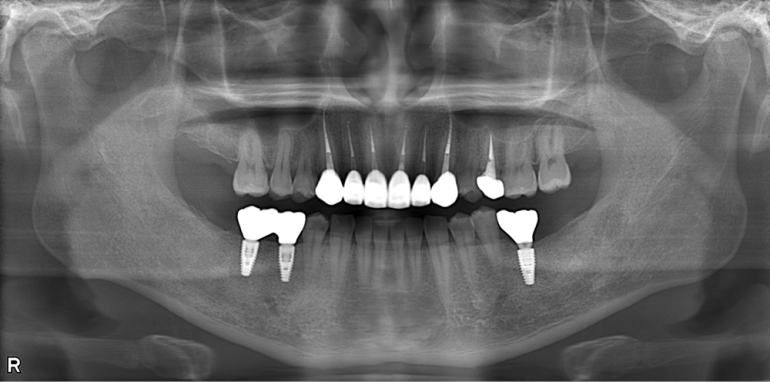

歯がボロボロで恥ずかしい方へ

tattered_teeth_case02_after02